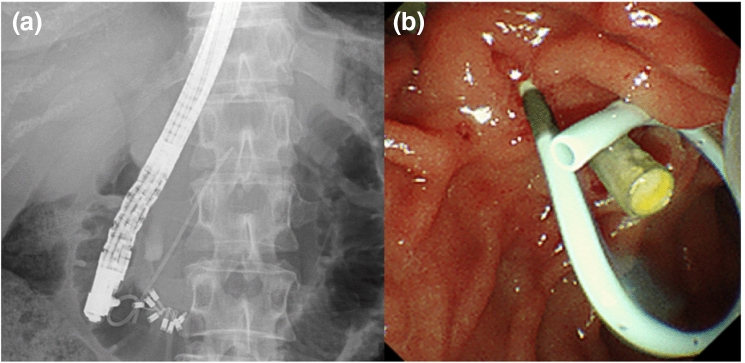

Endoscopic procedures

All patients underwent ERCP using a duodenoscope (TJF-260V; Olympus Medical Systems, Tokyo, Japan) under conscious sedation. Cannulation was attempted using a standard injection catheter (ERCP catheter, MTW Co., Dusseldorf, Germany) or sphincterotome (CleverCut; Olympus Medical Systems, Tokyo, Japan) with a 0.025-in. guidewire (VisiGlide 2, Olympus Medical Systems, Tokyo, Japan). We used a newly designed 4-Fr pancreatic duct stent with varying lengths of 3, 5, 7, and 9 cm. The stent had a tapered tip, three internal flanges (one at the distal end and two at the proximal end), and a single external pigtail (Fit Stent 025: Gadelius Medical Co., Ltd., Tokyo, Japan) (Fig. 1). The stent could pass over a 0.025-in. guidewire under fluoroscopic guidance.

Figure 1:

4-Fr pancreatic stent. The stent has a tapered tip, three internal flanges (one at the distal end and two at the proximal end), and a single external pigtail with a black marker on the proximal side.

The patients underwent subsequent pancreatic duct cannulation, contrast injection, and guidewire insertion for stent placement. We selected the length of the stent based on the degree of flexion and the length of the pancreatic duct in the head of the pancreas. The stent was passed over a guidewire under fluoroscopic guidance (Fig. 2). Following ERCP, the patients were requested to fast until their blood tests confirmed no pancreatitis or other complications, the following day. All patients were hospitalized for ERCP and observation. The stent was planned to be removed duodenoscopically between the third to seventh day in cases of prophylactic pancreatic stent placement, if it had not been dislodged. However, it was planned to be removed based on the symptoms in case of pancreatic duct drainage. The conventional 5-Fr pancreatic duct stent placement was the same as those for 4-Fr pancreatic duct stent. All ERCP procedures were performed by experts (> 5 years of ERCP experience) or by trainees (< 5 years of ERCP experience) under the direction of an expert.

Figure 2.

A case of pancreatic duct stenting using the novel 4-Fr plastic stent. (a) Fluoroscopy, The 4-Fr stent has been placed in the pancreatic duct; (b) Endoscopy, The single-pigtail and the black marker of the proximal side are exposed to the duodenum.